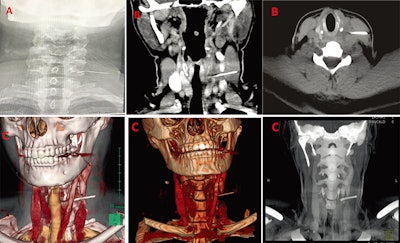

10. 3-cm swallowed dental needle removed from patient's neck

Clinicians removed a 3-cm needle from a patient who swallowed it, likely during a dental procedure, according to a recent case report published in the Journal of Dental Anesthesia and Pain Medicine. This was believed to be the first reported case of an ingested dental needle causing neck pain.

A: An x-ray showed a long, thin, and impinged foreign body. B: CT confirmed that the body was metallic and 3 cm in length. C: 3D reconstructed images were used for planning the removal of the needle. Image courtesy of Hassen Mohammed, MD, et al. Licensed under CC BY-NC 4.0.